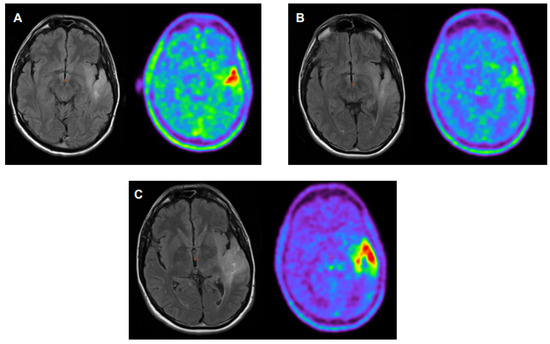

- Galldiks, N.; Dunkl, V.; Stoffels, G.; Hutterer, M.; Rapp, M.; Sabel, M.; Reifenberger, G.; Kebir, S.; Dorn, F.; Blau, T.; et al. Diagnosis of pseudoprogression in patients with glioblastoma using O-(2-[18F]fluoroethyl)-L-tyrosine PET. Eur. J. Nucl. Med. Mol. Imaging 2015, 42, 685–695. [Google Scholar] [CrossRef] [PubMed]

- Kebir, S.; Fimmers, R.; Galldicks, N.; Schäfer, N.; Mack, F.; Schaub, C.; Stuplich, M.; Niessen, M.; Tzaridis, T.; Simon, M.; et al. Late Pseudoprogression in Glioblastoma: Diagnostic Value of Dynamic O-(2-[18F]fluoroethyl)-L-Tyrosine PET. Clin. Cancer Res. 2016, 22, 2190–2196. [Google Scholar] [CrossRef] [PubMed]